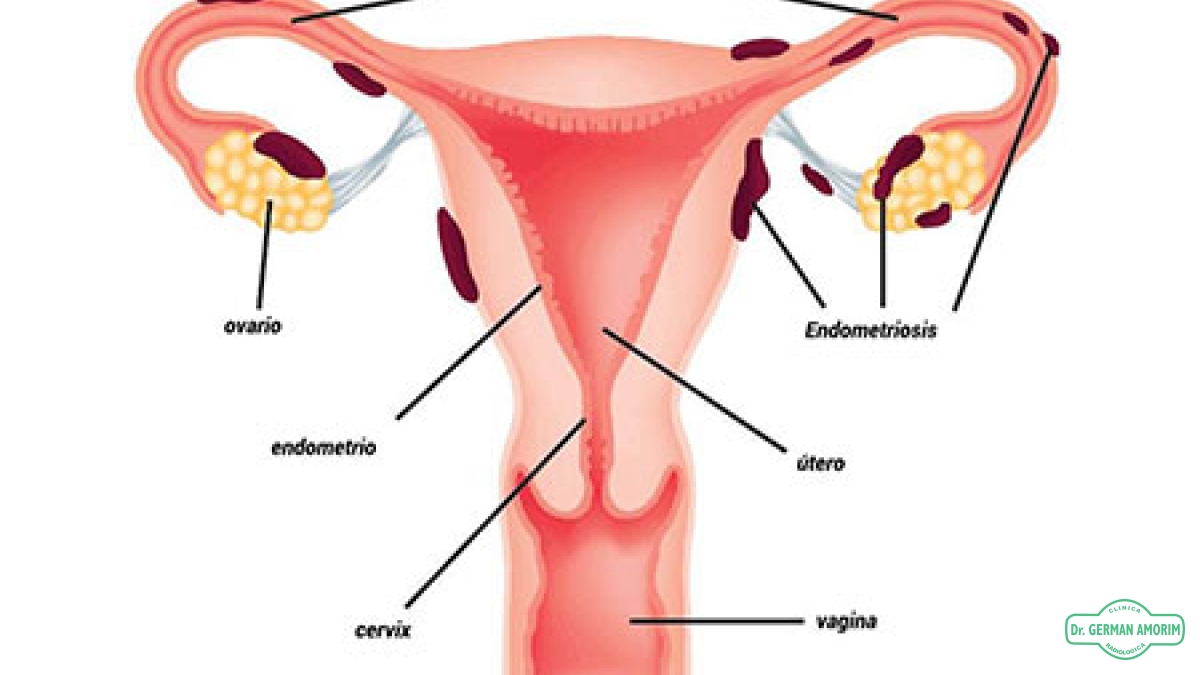

A diferencia de los hombres, que producen espermatozoides a lo largo de toda la vida, las mujeres nacen con un número determinado de óvulos. Al llegar a la pubertad, la mujer comienza a ovular todos los meses; en el momento de la menopausia, la reserva de óvulos ha quedado agotada y consecuentemente la mujer pierde la fertilidad.

El folículo antral (en reposo) es una pequeña esfera llena de líquido que contiene un óvulo inmaduro. Los folículos son visibles y pueden contarse mediante una ecografía los días segundo, tercero y quinto del ciclo menstrual. El número de folículos antrales varía cada mes.

El recuento de folículos antrales, junto con la edad y el perfil hormonal del día 3, es uno de los mejores indicadores de la reserva ovárica y de la capacidad de que la mujer consiga la gestación con la fecundación in vitro (FIV). Dicho de otro modo, los folículos antrales predicen el número de folículos maduros (dominantes) que podremos estimular con los medicamentos que se administran antes de la FIV. El número de óvulos que obtengamos guarda relación directa con las tasas de éxito de la FIV.